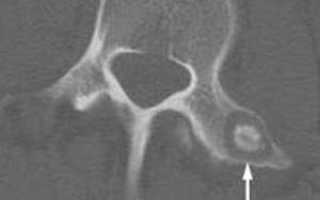

Остеома определяется на основе рентгеновского снимка затронутых костей. Для более глубокого анализа врач может назначить компьютерную томографию, которая позволяет точно определить местоположение опухоли и ее характеристики.

На этом рентгеновском снимке четко демонстрируется расположение опухоли: